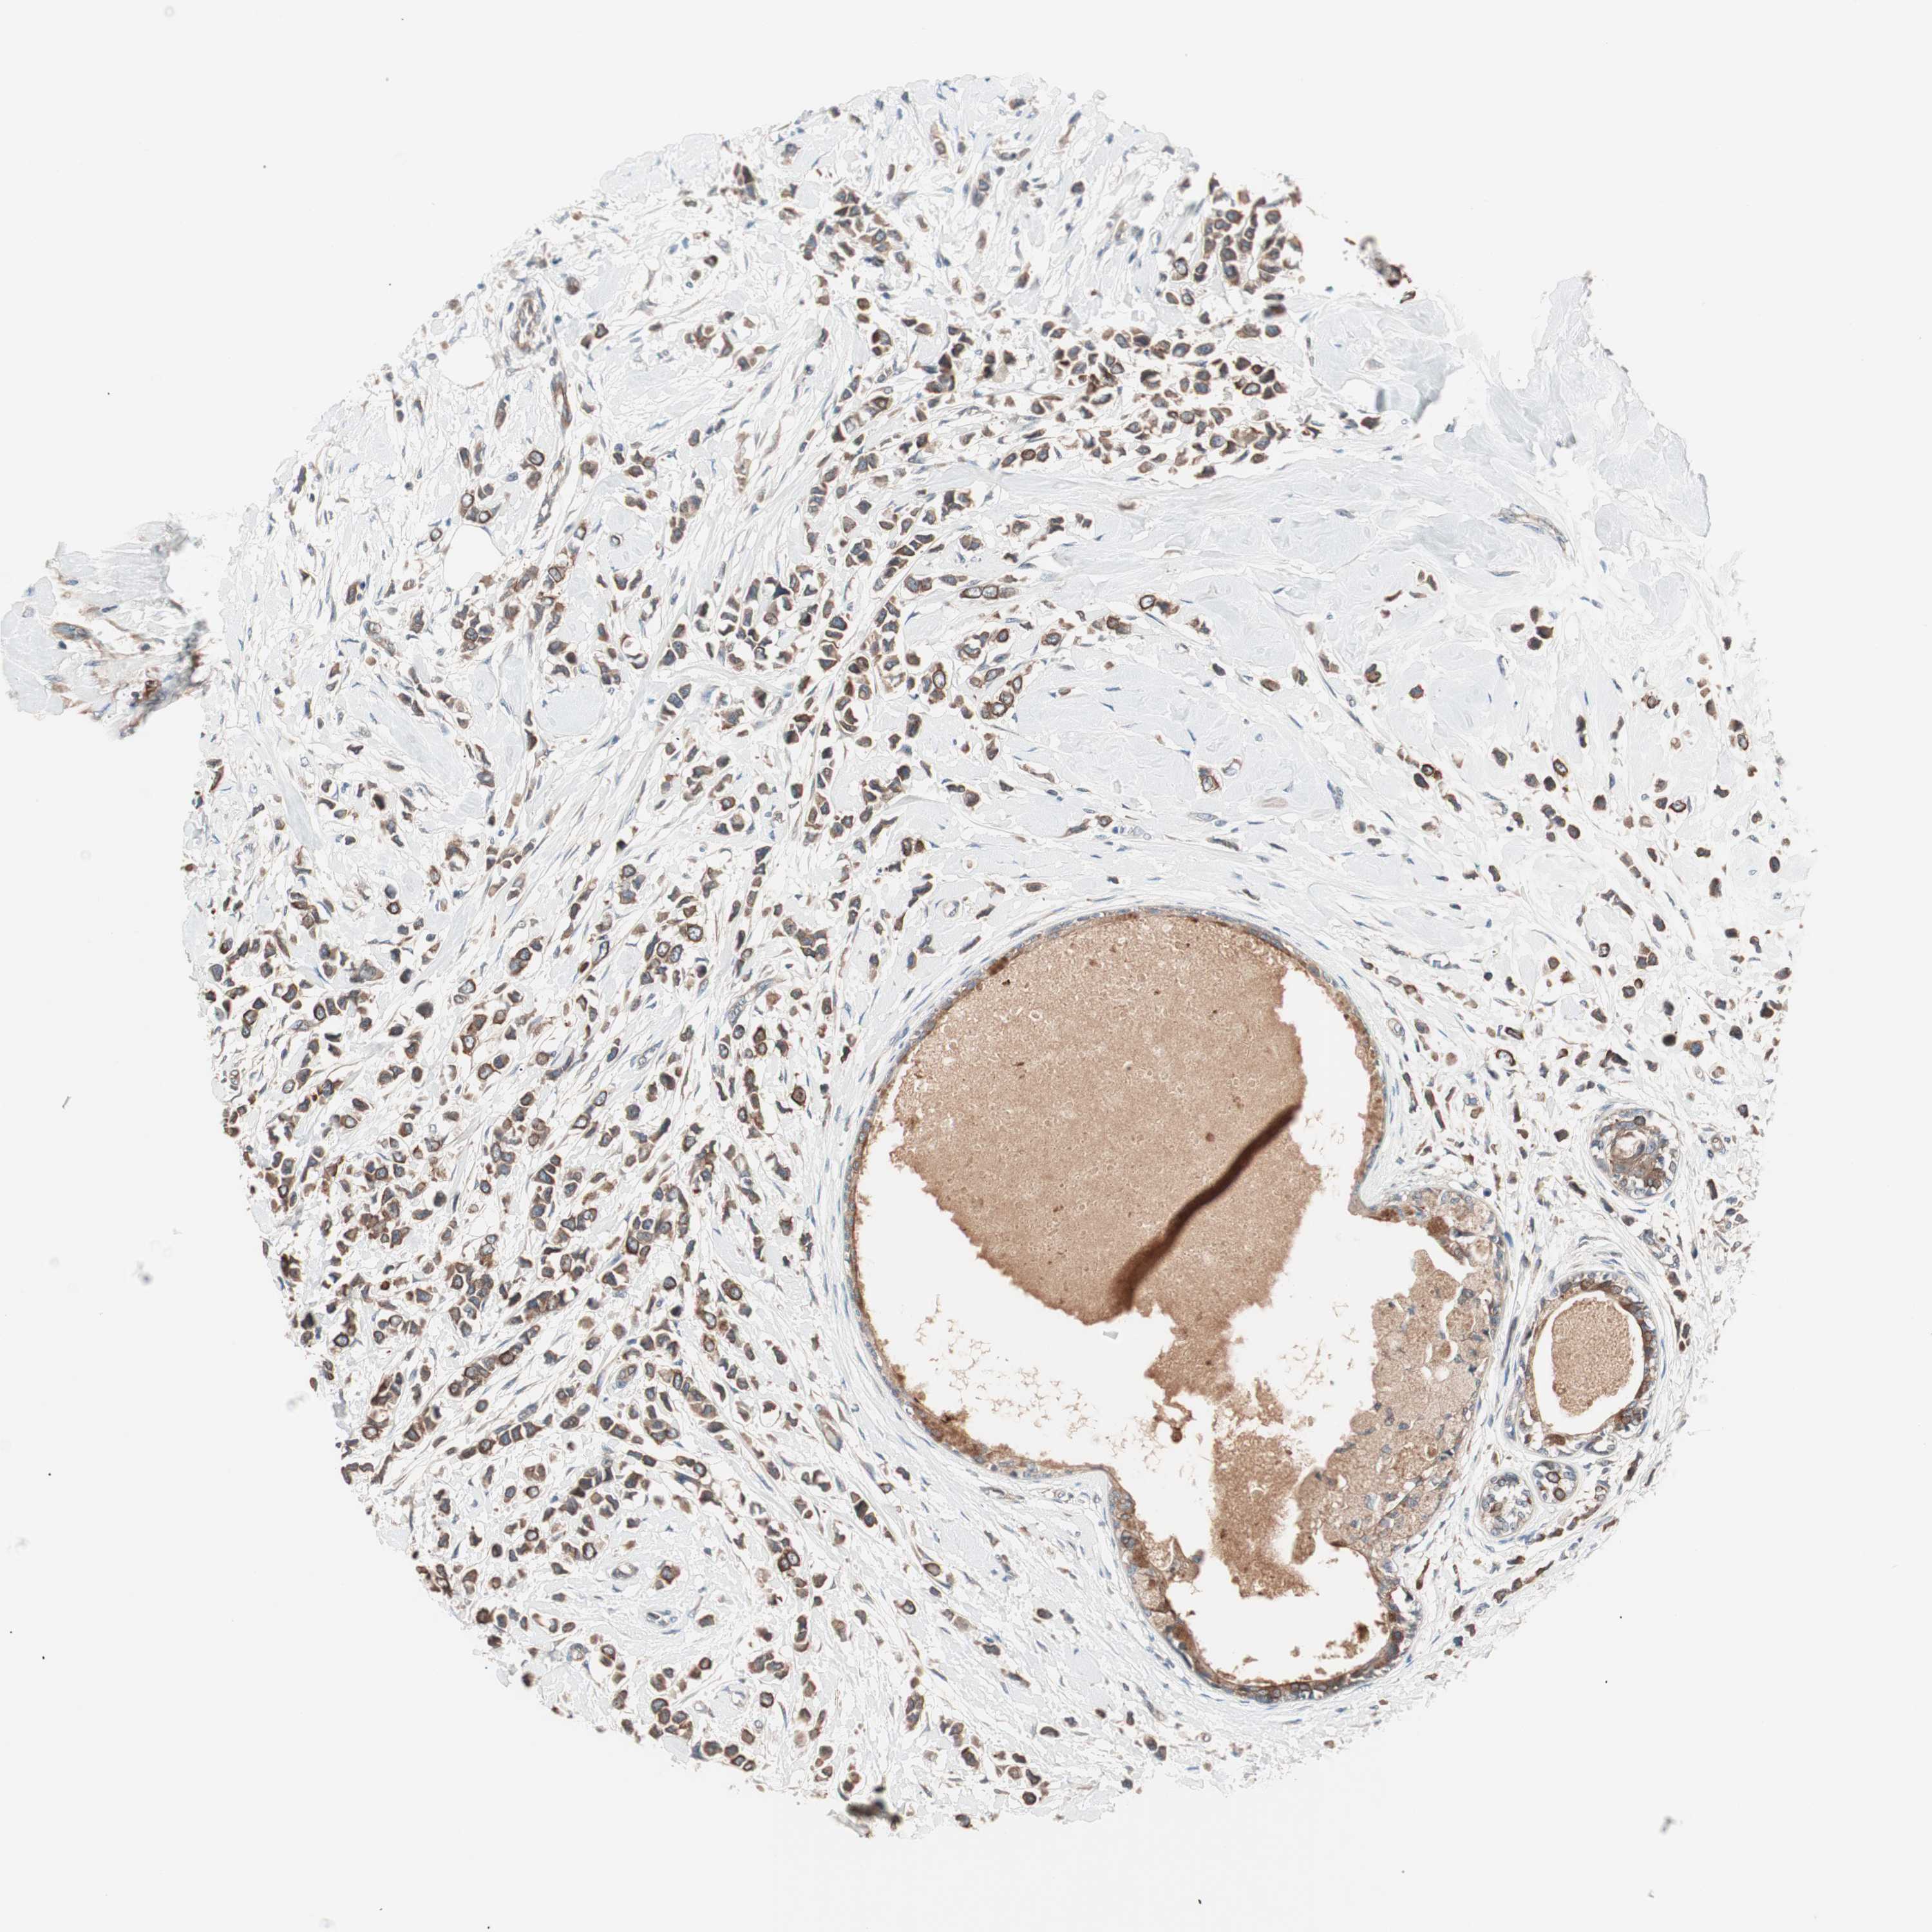

CANCER BREAST CANCER Show tissue menu

BRCA TCGA BRCA VALIDATION PROTEIN EXPRESSION